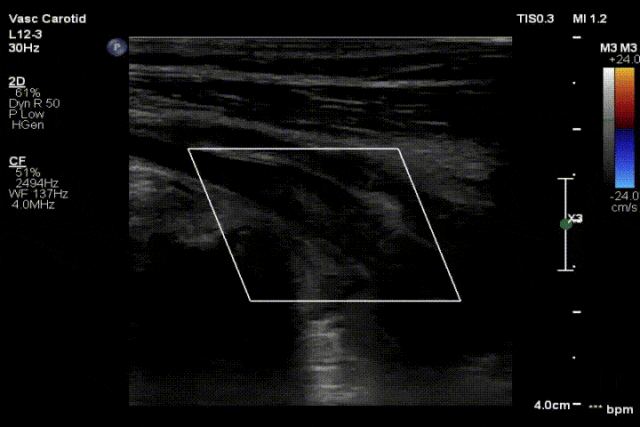

图:a) 穿刺后导丝置入;

图:b) 吸栓装置定位;

图:c) 球囊扩张股浅动脉时球囊远心端显像;

图:d)球囊扩张股浅动脉开口处显像,同时附带血流显像;

图:e)术前评估时腘动脉未见血流图像;

图:f)经吸栓、球囊扩张等治疗措施后腘动脉血流图像